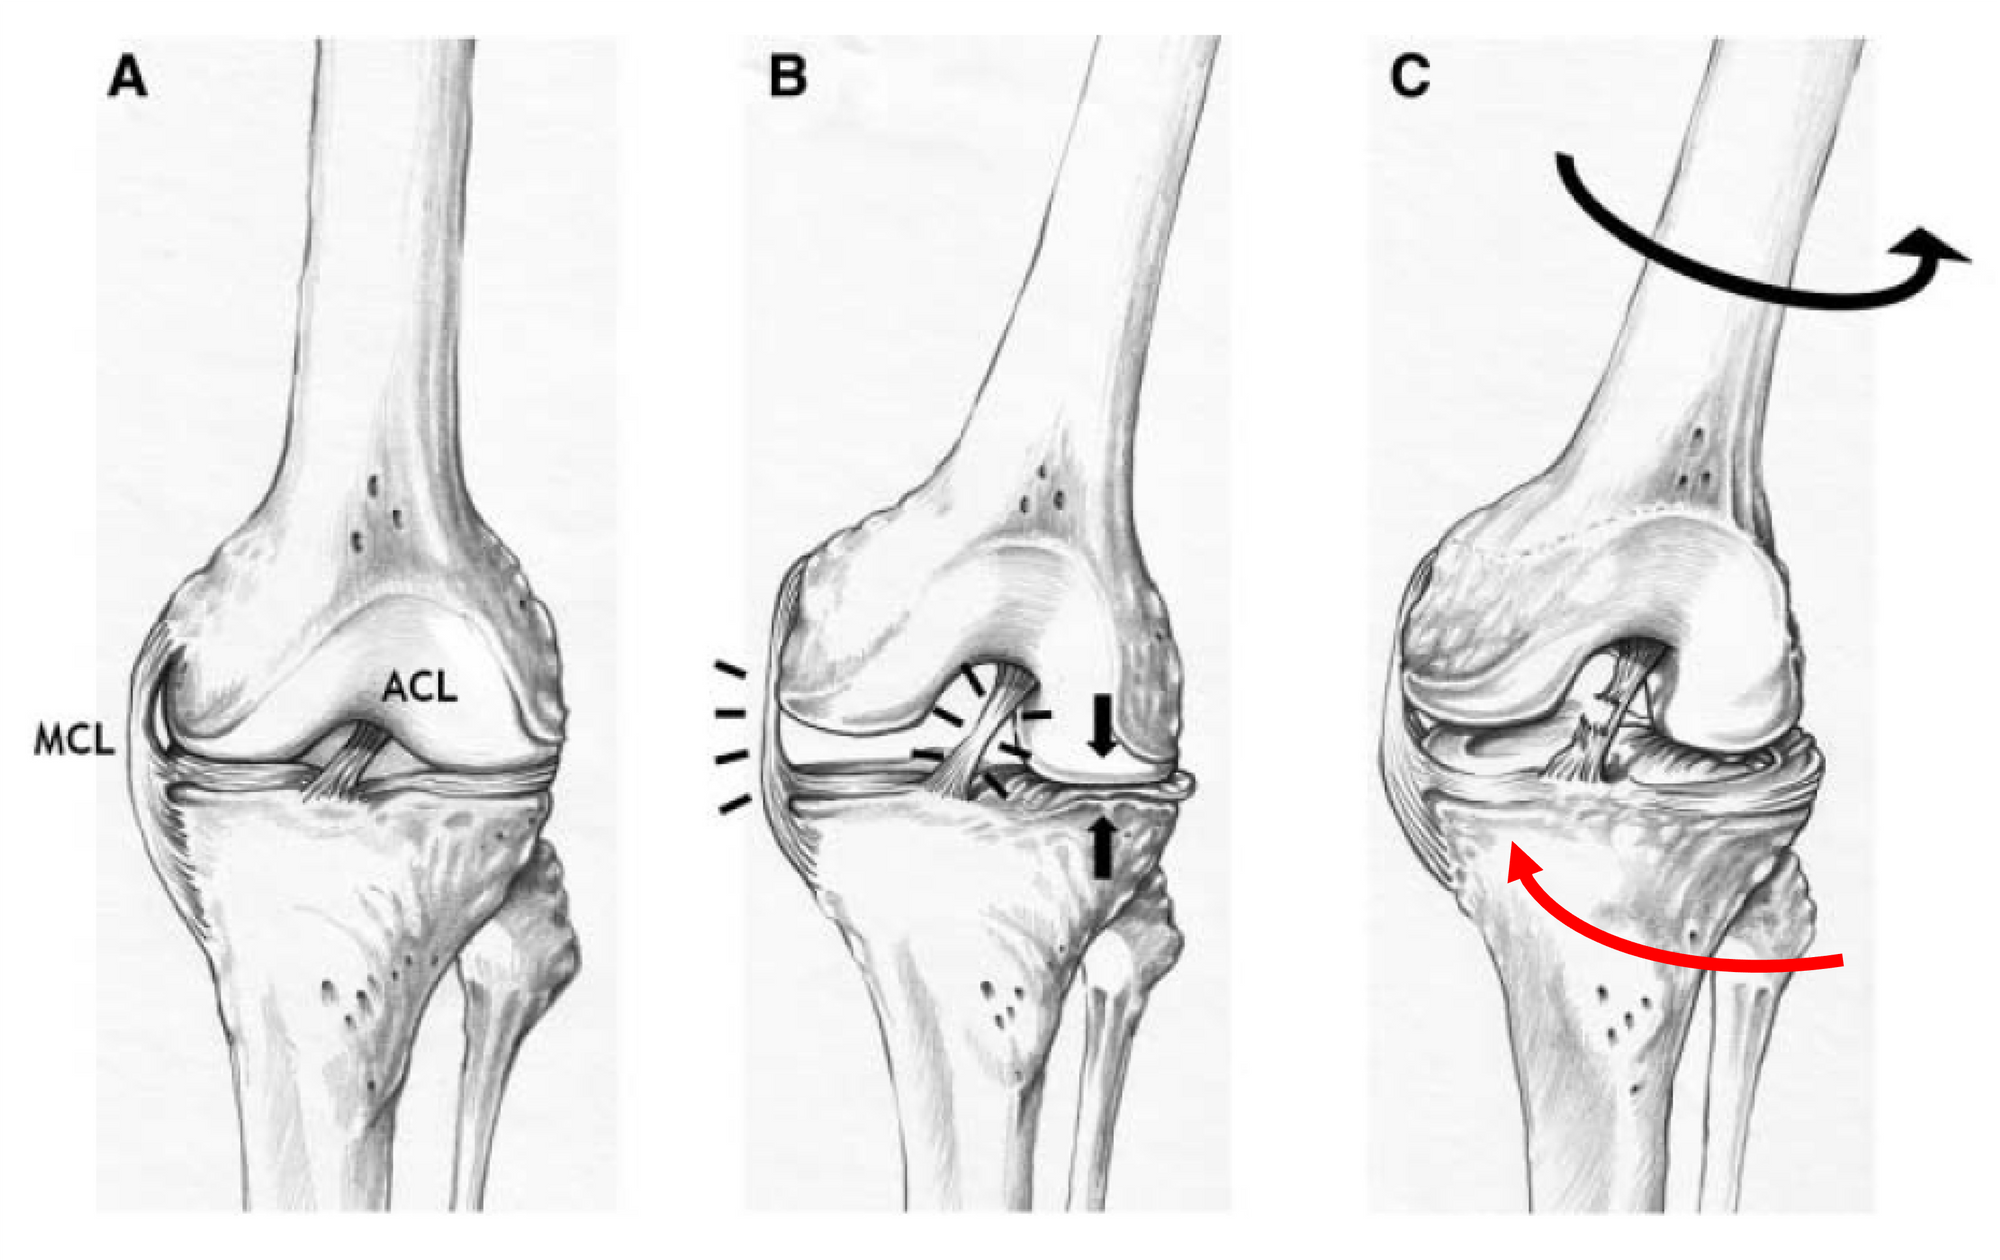

Using the same technique to analyse the kinematics of non-contact ACL rupture among ten female handball and basketball players, Koga et al. hypothesised the mechanism of injury (Figure 5) (22).

In the initial phase, a valgus stress is applied, causing tension in the medial collateral ligament (MCL) and compression in the lateral compartment. This compressive load, together with the anterior force vector caused by the quadriceps contraction, causes a displacement of the femur relative to the tibia. While the lateral femoral condyle moves backward, the tibia moves forward and internally rotates, resulting in a rupture of the ACL. Once this occurs, the main restriction to the anterior translation of the tibia disappears. The lateral femoral condyle is also displaced posteriorly, causing the medial condyle to move posteriorly and resulting in external rotation of the tibia.